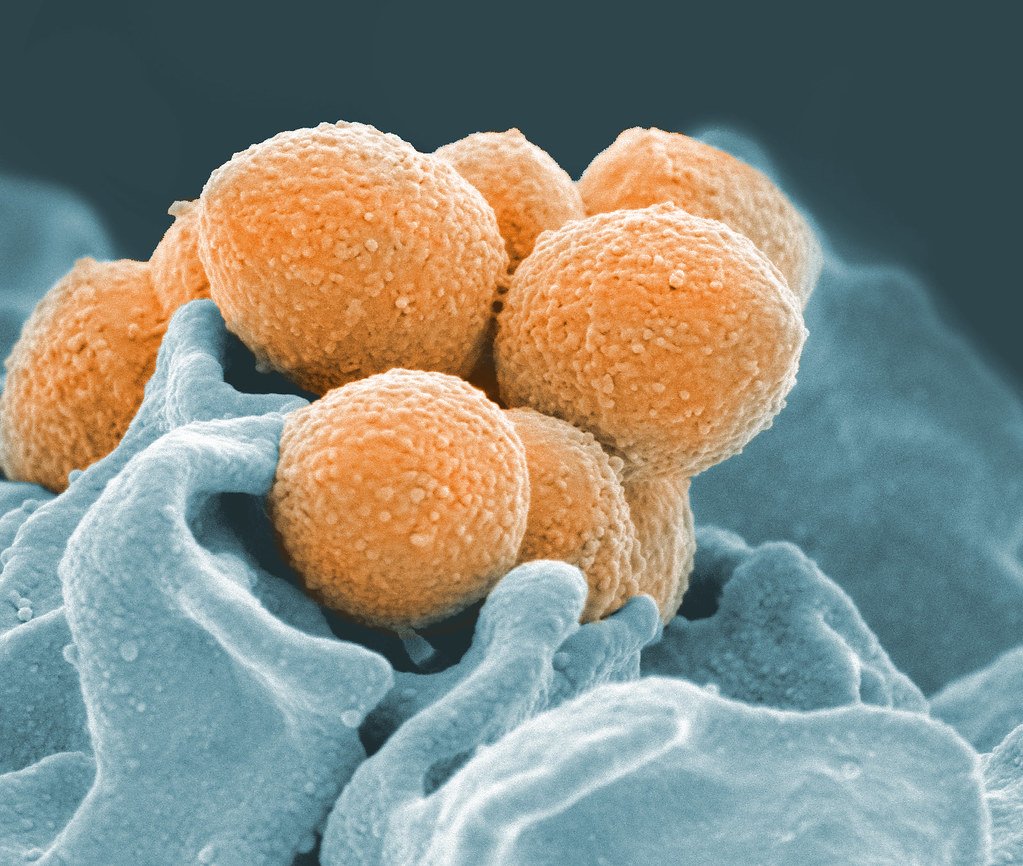

3. Smrteľné baktérie manipulujú s bolesťou

Baktéria Streptococcus pyogenes, ktorá spôsobuje tzv. chorobu požierajúcu mäso, dokáže uniesť receptory bolesti. Uvoľňuje toxín, ktorý nielenže spôsobuje extrémnu bolesť, ale zároveň potláča imunitnú reakciu tela. Zaujímavosťou je, že injekcia botoxu dokáže blokovať tento proces a pomôcť telu v boji proti infekcii.